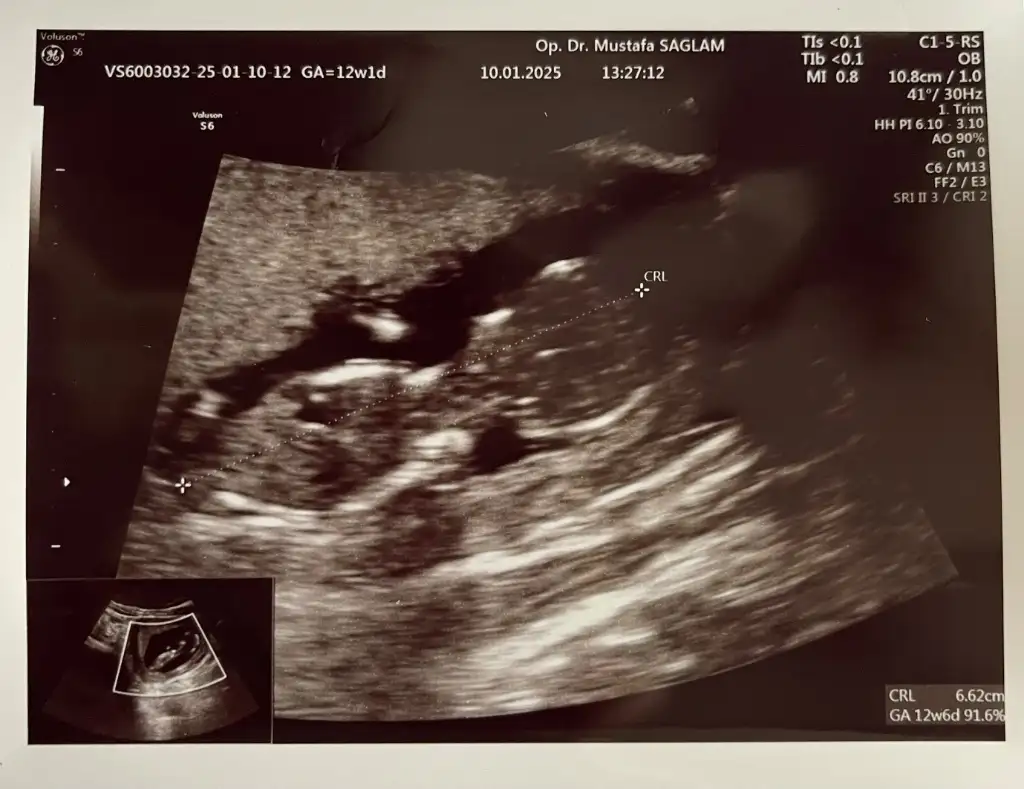

Buda 12+2 haftalık hala aynı fikirde misiniz?Kıza benzettim ben

Buda 12+2 haftalık hala aynı fikirde misiniz acaba ?Annesi maşallah tosununayanlış görmüyorsam oğlumdaki aynı çıkıntı burada da, sağlıcakla gelsin inşallaaaah,

Evet hala erkeğe benzettimBuda 12+2 haftalık hala aynı fikirde misiniz?

Kızzz